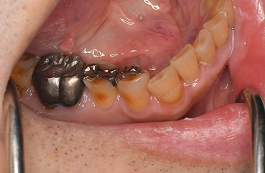

歯ぎしり・食いしばり治療の症例紹介

症例紹介①

| 患者さまのお悩み | |

|---|---|

| 治療内容 | |

| 年齡 | |

| 性別 | |

| 治療期間 | |

| 治療費 | |

| 治療で得られるメリット | |

| 治療する際に起こる リスク・副作用 |